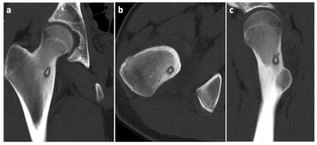

Tratamentul Minim Invaziv al Osteomului Osteoid prin Ablația cu Radiofrecvență

Osteomul osteoid este o formațiune tumorală osoasă benignă activă, de mici dimensiuni, care afectează de obicei persoanele tinere, în spe...